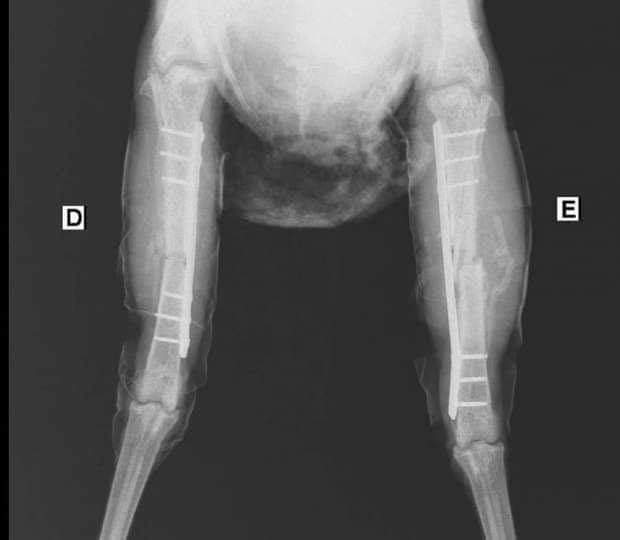

جدير بالذكر طبيبان بيطريان قد أجريا عملية جراحية لفرخة بها كسر، وتم تركيب شرائح ومسامير طبية لها، ويطلق عليها اسم "ليكسي"، ووضعت تحت الملاحظة، وتم وضعها على أجهزة وتركيب محاليل لها بديلًا عن الطعام حتى الإنتهاء من إجراء العملية الجراحية لها.